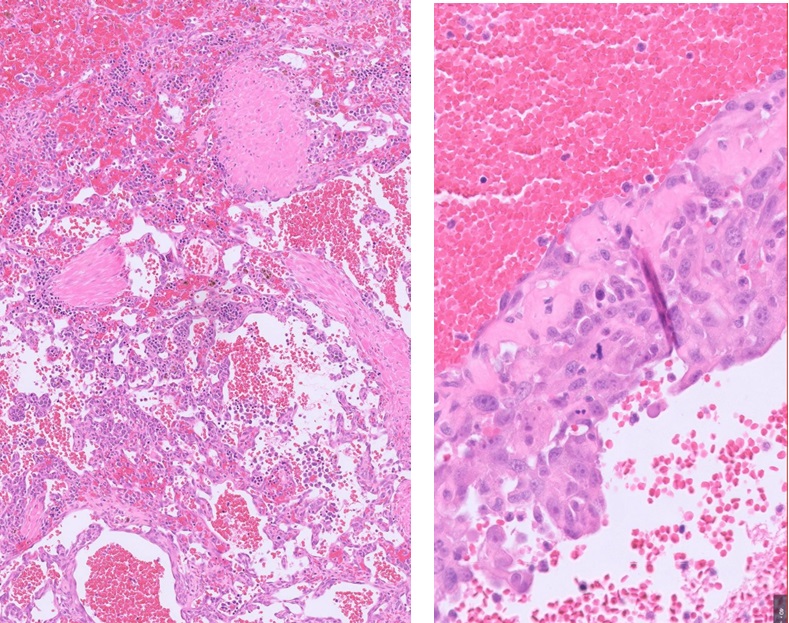

If sending the entire organ is not feasible, then submission of selected, representative sections is the next best option, ideally supported by annotated photographs. When sampling nodules, we strongly advise sampling of the transition area between the nodule and the surrounding spleen. Sampling the centre is likely to capture only blood and may miss more diagnostic peripheral tissue, particularly in haemangiosarcoma (see Fig 1).